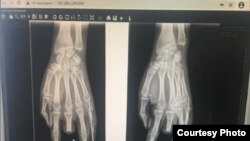

Гуля Белек кызынын жабыркаган колунун рентгенге түшүрүлгөн сүрөтү.